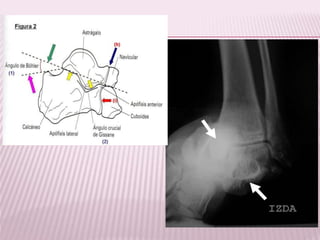

CALCANEO

 Fracturas talámicas

 Fracturas extratalámicas

Mas frecuentes, pero mas

complicadas de tratar.

Mejor pronostico

TALAMICA

S

EXTRATALAMIC

AS

Se produce por lo general por una

caída desde una altura variable,

Mejor pronóstico, comprenden

las fracturas de la tuberosidad

mayor.

ASTRAGALO

 Cabeza

 Cuello

 Cola

Su incidencia oscila entre el 0,1% y el

0,85% de todas las fracturas.

Representan el 50% de las fracturas, mecanismo:

caída desde cierta altura con pie en flexión

dorsal.

Clasificación Hawkins:

I. Sin desplazamiento, alineación

normal de la articulación

subastragalina

II. Desplazada y asociada con

subluxación o luxación de la

articulación subastragalina

III. Desplazada y asociada con

luxación completa de la articulación

subastragalina como

tibioastragalina.